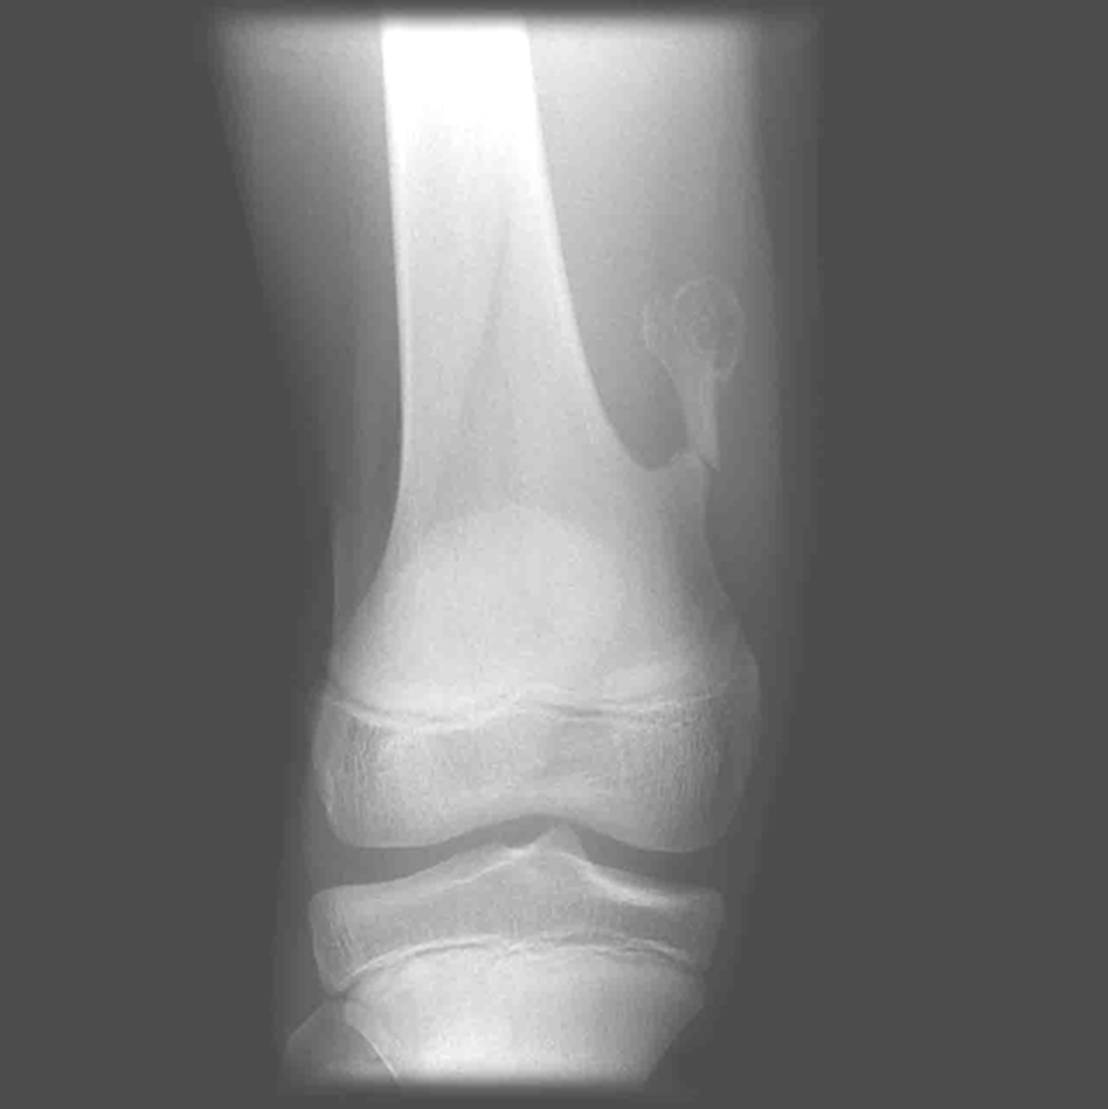

Osgood Schlatter

Incomplete separation or avulsion of the tibial tuberosity.

Cause: Repeated stress to tibial tuberosity growth plate

•stress will lead to the tendon pulling away

Complications: are uncommon, chronic pain or localized swelling,

bump in the area

Radiographic Appearance: prominent soft tissue swelling and an avulsed ossific fragment

Technical: No manual exposure factor change

Prognosis: good, resolves normally on its own once the bones

stop growing